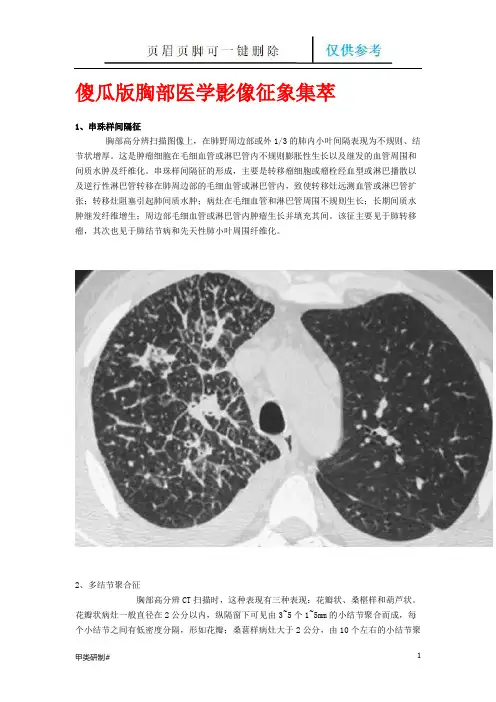

傻瓜版胸部医学影像征象集萃1、串珠样间隔征胸部高分辨扫描图像上,在肺野周边部或外1/3的肺内小叶间隔表现为不规则、结节状增厚。

这是肿瘤细胞在毛细血管或淋巴管内不规则膨胀性生长以及继发的血管周围和间质水肿及纤维化。

串珠样间隔征的形成,主要是转移瘤细胞或瘤栓经血型或淋巴播散以及逆行性淋巴管转移在肺周边部的毛细血管或淋巴管内,致使转移灶远测血管或淋巴管扩张;转移灶阻塞引起肺间质水肿;病灶在毛细血管和淋巴管周围不规则生长;长期间质水肿继发纤维增生;周边部毛细血管或淋巴管内肿瘤生长并填充其间。

该征主要见于肺转移瘤,其次也见于肺结节病和先天性肺小叶周围纤维化。